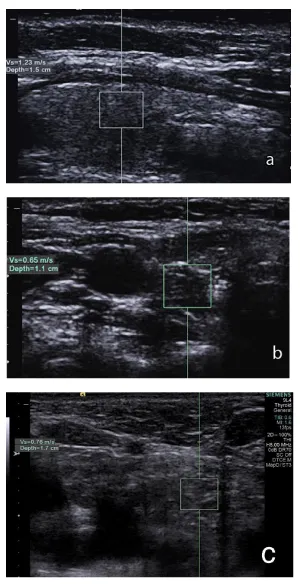

A second ultrasonography was performed in our institution with Siemens Acuson S2000™ ultrasound system using an L9-4 MHz transducer. A 6x6x8 mm sized ovoid lesion in the right lower pole of thyroid was detected. The lesion had no distinct border to thyroid tissue, which leads us to think of an intrathyroidal localization. The lesion was hypoechoic and had multiple milimetric bright internal echoes on gray-scale ultrasonography. Doppler ultrasonography did not show a significant vascularity (Figure 1). Because of the similarity in gray scale and Doppler ultrasonography imaging findings to thymus when compared, the lesion was thought to be an ectopic intrathyroidal thymus (Figure 2). We performed ARFI elastography to support the diagnosis. ARFI elastography measurements from the normal thyroid parenchyma, from the lesion in the right lower pole of thyroid and from the anterior mediastinal thymus were done (Figure 3). Each measurement was repeated for five times and the mean value was recorded. The mean ARFI elastography velocities of the lesion and the mediastinal thymus were, 0, 63 m/s and 0, 60 m/s, respectively. The mean ARFI elastography velocity of the normal thyroid parenchyma was 1, 25 m/s. The normality of data distribution was evaluated with Saphiro-Wilk test and Paired sample T test was used to compare the mean SWVs in normal distributed data. There was not a significant difference between the mean SWV of the lesion and thymus (p=0.9). There was a significant difference between the mean SWV of the lesion and thymus versus thyroid gland (p=0.001 and p=0.002, respectively). The lesion was diagnosed as ectopic intrathyroidal thymus and follow-up was recommended.

Several cases of intrathyroidal ectopic thymus in children had previously been reported. Most commonly these lesions were misdiagnosed as a thyroid nodule on ultrasonography. In the previous cases, CT, MRI or sintigraphy had been used as conformational imaging studies [13]. Some of these patients underwent surgery for excision or biopsy was performed to exclude malignancy. To our knowledge this is the first time in the literature that the diagnosis was supported with ARFI elastography findings without the need for any other procedure. Although studies were carried out for ARFI elastography measurements of thyroid nodules and diffuse thyroid diseases in adults, to our knowledge, elastography values of normal or abnormal thyroid tissue in children had not been reported in the literature. Sporea et al., reported the means of ARFI in thyroid gland in healthy subjects as 2±0, 40 m/s [8]. Friedrich-Rust et al., in their study evaluating ARFI imaging in the thyroid gland; reported the median velocity in the healthy thyroid gland as 1.98 m/s, in benign thyroid nodules as 2.02 m/s, and in malignant thyroid nodules 4.30 m/s [5]. In their study, ARFI elastography values in benign nodules were similar to normal thyroid paranchyme whereas in malignant nodules elastography values were higher. In the present case, the mean velocity in the ectopic intrathyroidal thymus was similar to the mean velocity in the anterior mediastinal thymus, 0, 63 m/s and 0, 60 m/s, respectively. The mean ARFI elastography value in the normal thyroid parenchyma was significantly different from the previous two measurements, 1, 25 m/s.